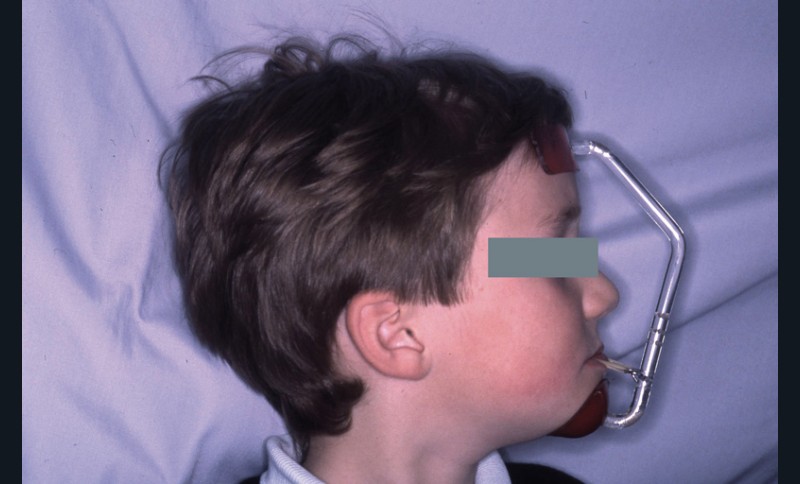

Ce bilan indique l’utilisation de tractions postéro-antérieures sur masque de Delaire dès maintenant et fait apparaître un pronostic réservé compte tenu de la dolichocorpie et de la croissance mandibulaire à venir.

Pendant cette première étape de traitement, les tractions postéro-antérieures sont portées la nuit, soit 8 à 9 h /24 h, sur masque de Delaire pendant 13 mois, avec des tractions d’environ 800 g (fig. 7 à 9).